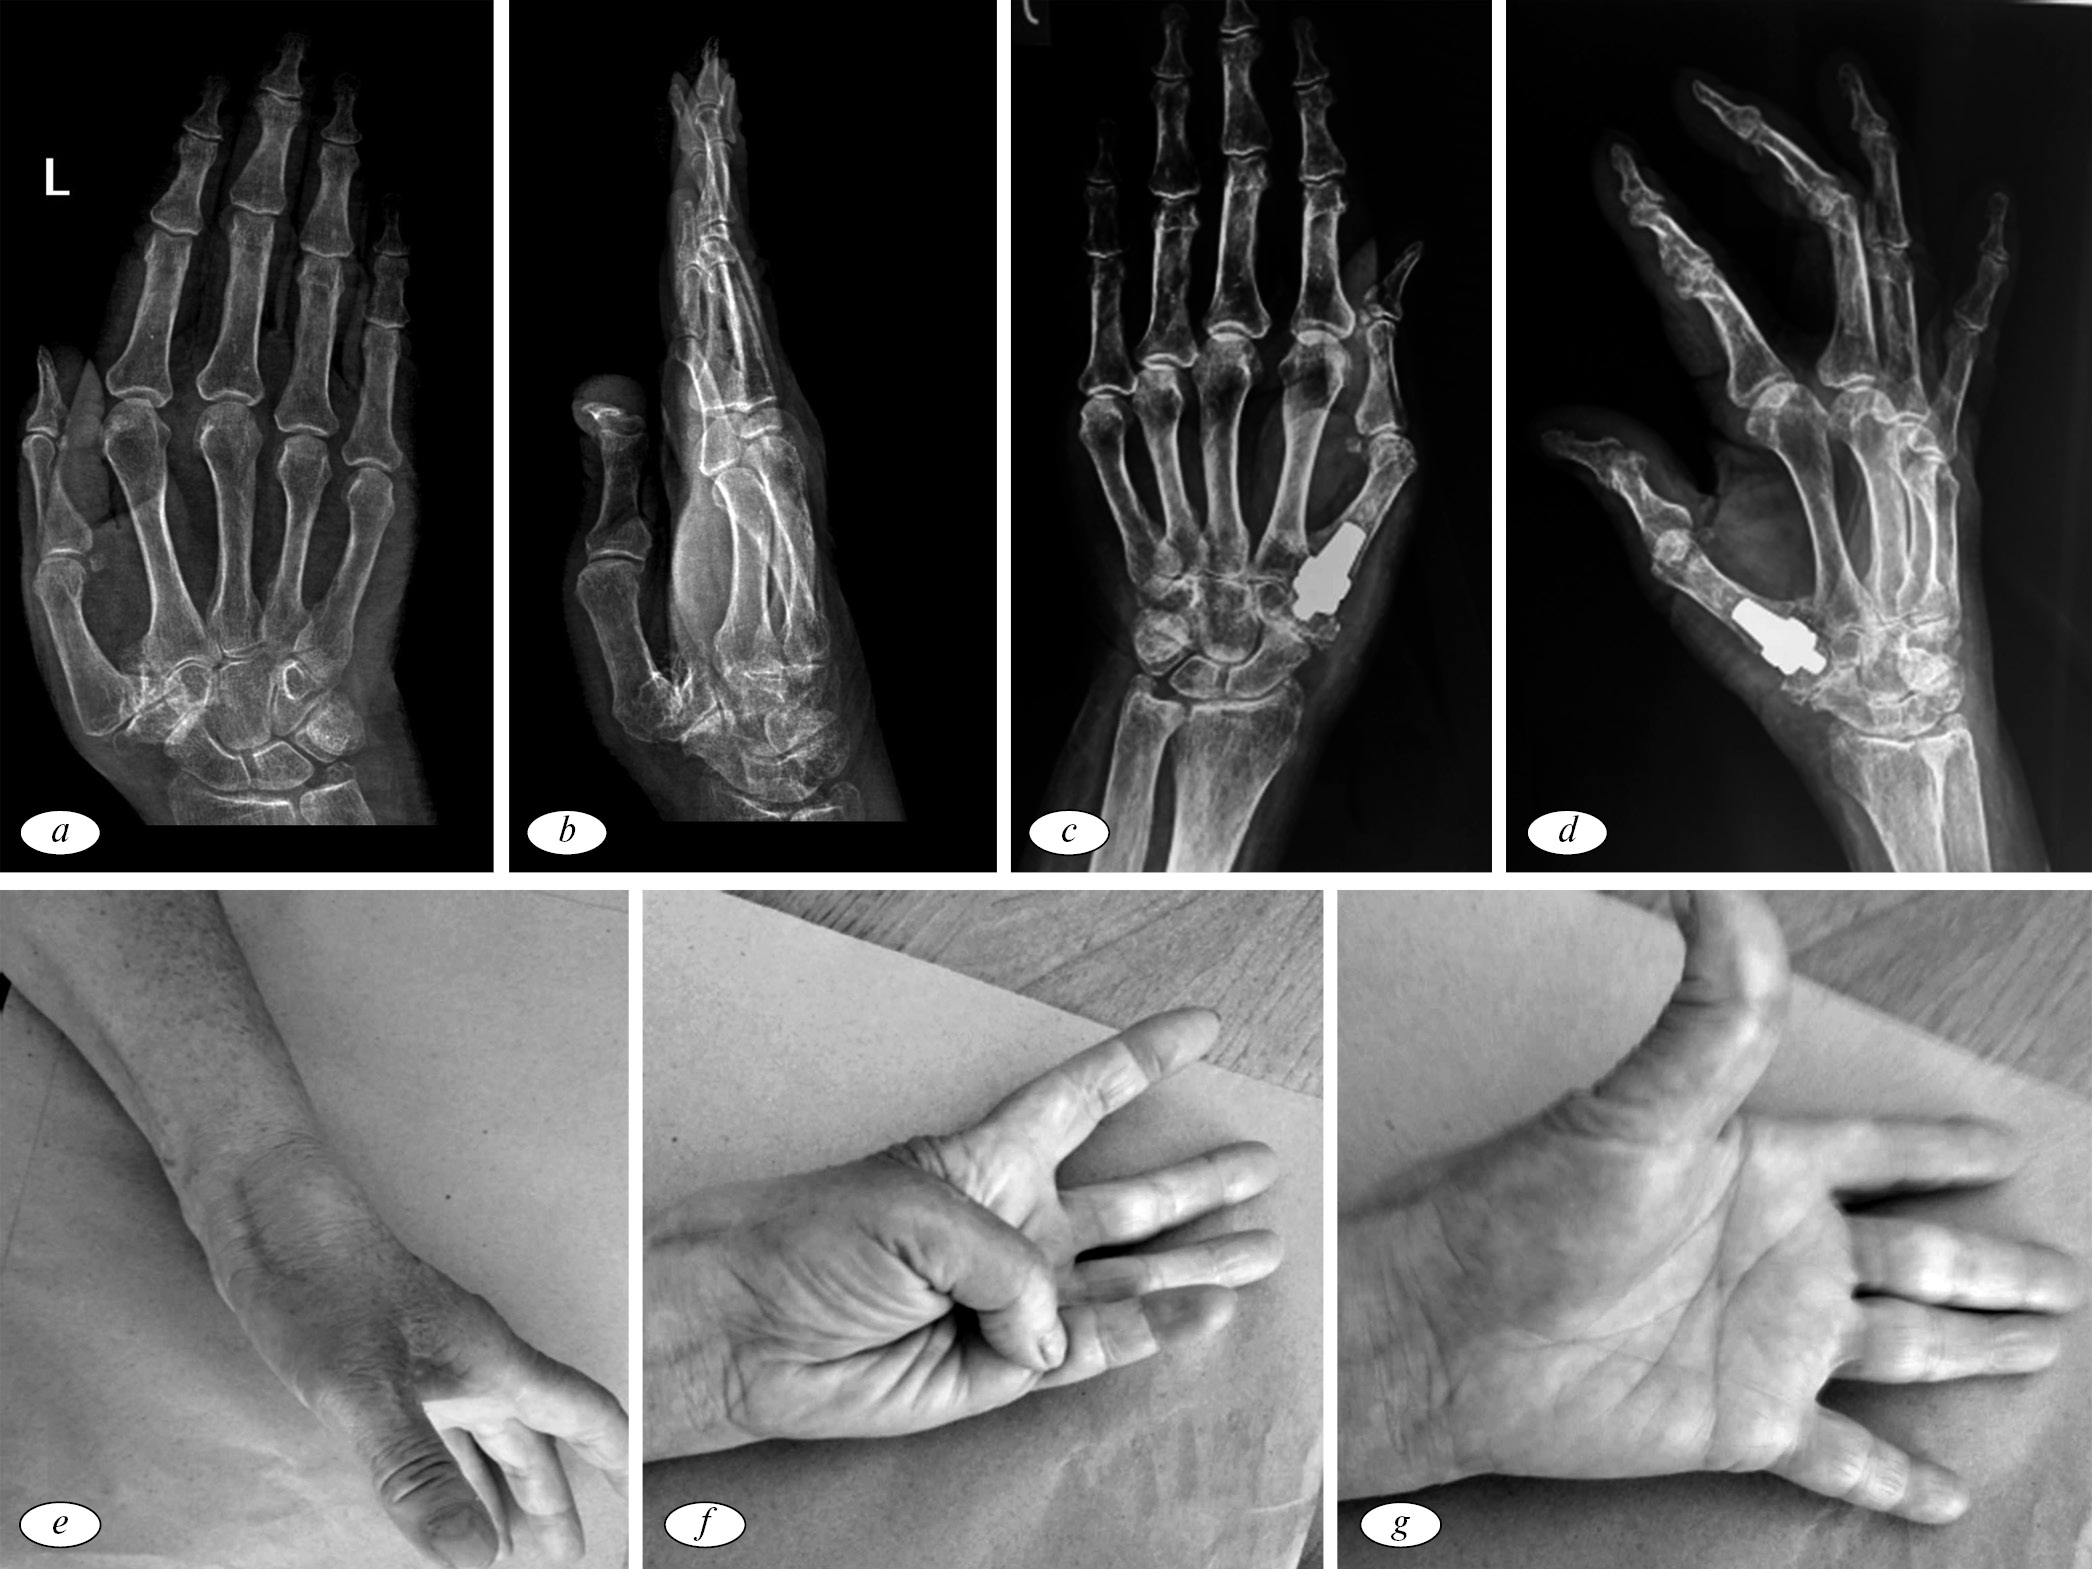

На первичном послеоперационном контрольном приеме все пациенты отмечали снижение болевых ощущений. Также отмечалось умеренное расширение объема движений на фоне сохраняющегося локального отека трапецие-пястного сустава. Рентгенологически было установлено, что во всех клинических случаях наблюдается стабильное положение компонентов, без признаков контактного остеолизиса или проседания. Через 1 год после оперативного вмешательства в 19 случаях (67,9 %) отмечалось отсутствие боли (0–1 балл по шкале ВАШ). В 9 случаях (25 %) — снижение болевых ощущений до значений в 2–3 балла. Все пациенты после операции без труда выполняли оппозицию (рис. 2), приведение и могли выполнить сложные действия (писать, рисовать). Некоторые обследуемые отметили улучшение почерка после оперативного вмешательства. Последняя особенность в полной мере зависела от снижения или отсутствия болевого синдрома.

Рис. 2. Рентгенограммы и внешний вид кисти: а, b — прямая боковая рентгенограмма кисти в предоперационном периоде; с, d — послеоперационные рентгенограммы кисти в прямой и боковой проекциях; e, f, g — функциональные тесты после оперативного лечения